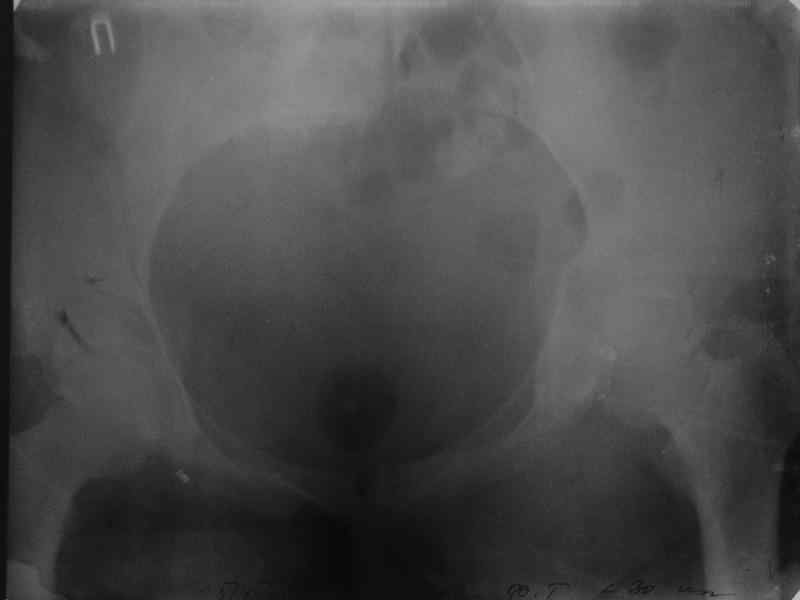

Здравствуйте, коллеги. Какие будут мнения по поводу лечения представляемой больной?

Молодая девушка 19 лет, травма 1 год назад, тогда же прооперирована.

В приложении снимки при поступлении и послеоперационные год назад.